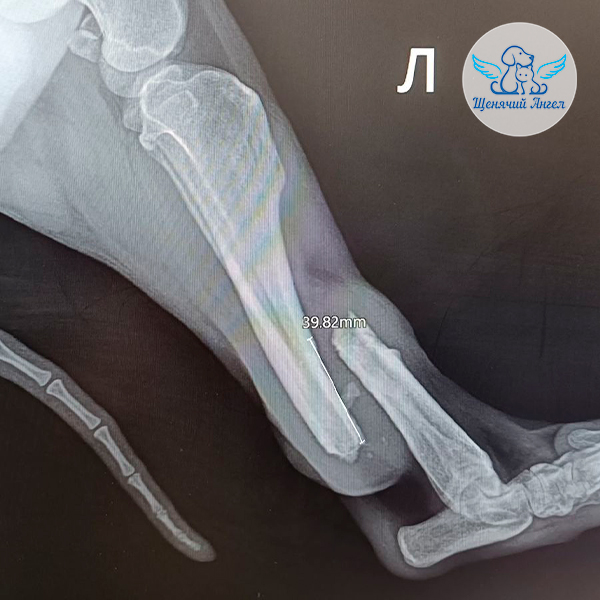

Хирург провёл диагностику и сделал рентген 🩻. У Капитана Барбоссы был застарелый поперечный перелом левой голени. Врач рекомендовал провести операцию остеосинтеза: соединить части сломанной косточки и закрепить их 🔩, чтобы они срослись правильно. А ещё предупредил ☝🏻, что, возможно, придётся укорачивать кость, так как перелом «несвежий»!

Капитан Барбосса без осложнений перенёс длительную операцию на большеберцовой кости и наркоз 🙏🏻. К сожалению, косточку всё-таки укоротили на 1,5 см, чтобы правильно совместить отломки. Поэтому врач прописал скорейшие занятия с реабилитологом 🐾👐🏻, чтобы восстановить возможность опираться на лапку и естественно двигаться 🐾.